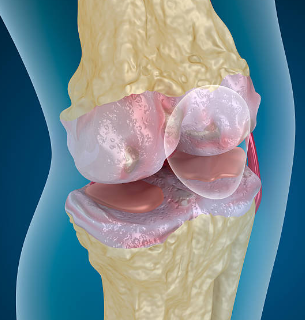

무릎에는 뼈가 서로 부딪히지 않도록 도와주는 “연골”이 있어요.

대표적으로 두 가지가 중요합니다.

첫째, 관절연골

무릎뼈 끝을 매끈하게 감싸서 마찰을 줄여주고 충격을 흡수해요.

둘째, 반월상연골(반달연골)

무릎 안쪽과 바깥쪽에 있는 반달 모양의 연골로, 체중이 한쪽에 쏠리지 않도록 분산해 주는 역할을 해요.

이 연골이 닳거나 찢어지거나 손상되면 무릎이 뻣뻣하고 아프고, 걷는 자세까지 달라지면서 다른 관절까지 무리가 가기 쉬워요.

연골은 혈관이 거의 없어서 “피가 통하면서 빨리 낫는 조직”이 아니에요. 그래서 작은 손상도 그냥 넘기지 말고, 초기에 관리해 줘야 회복이 훨씬 수월합니다.